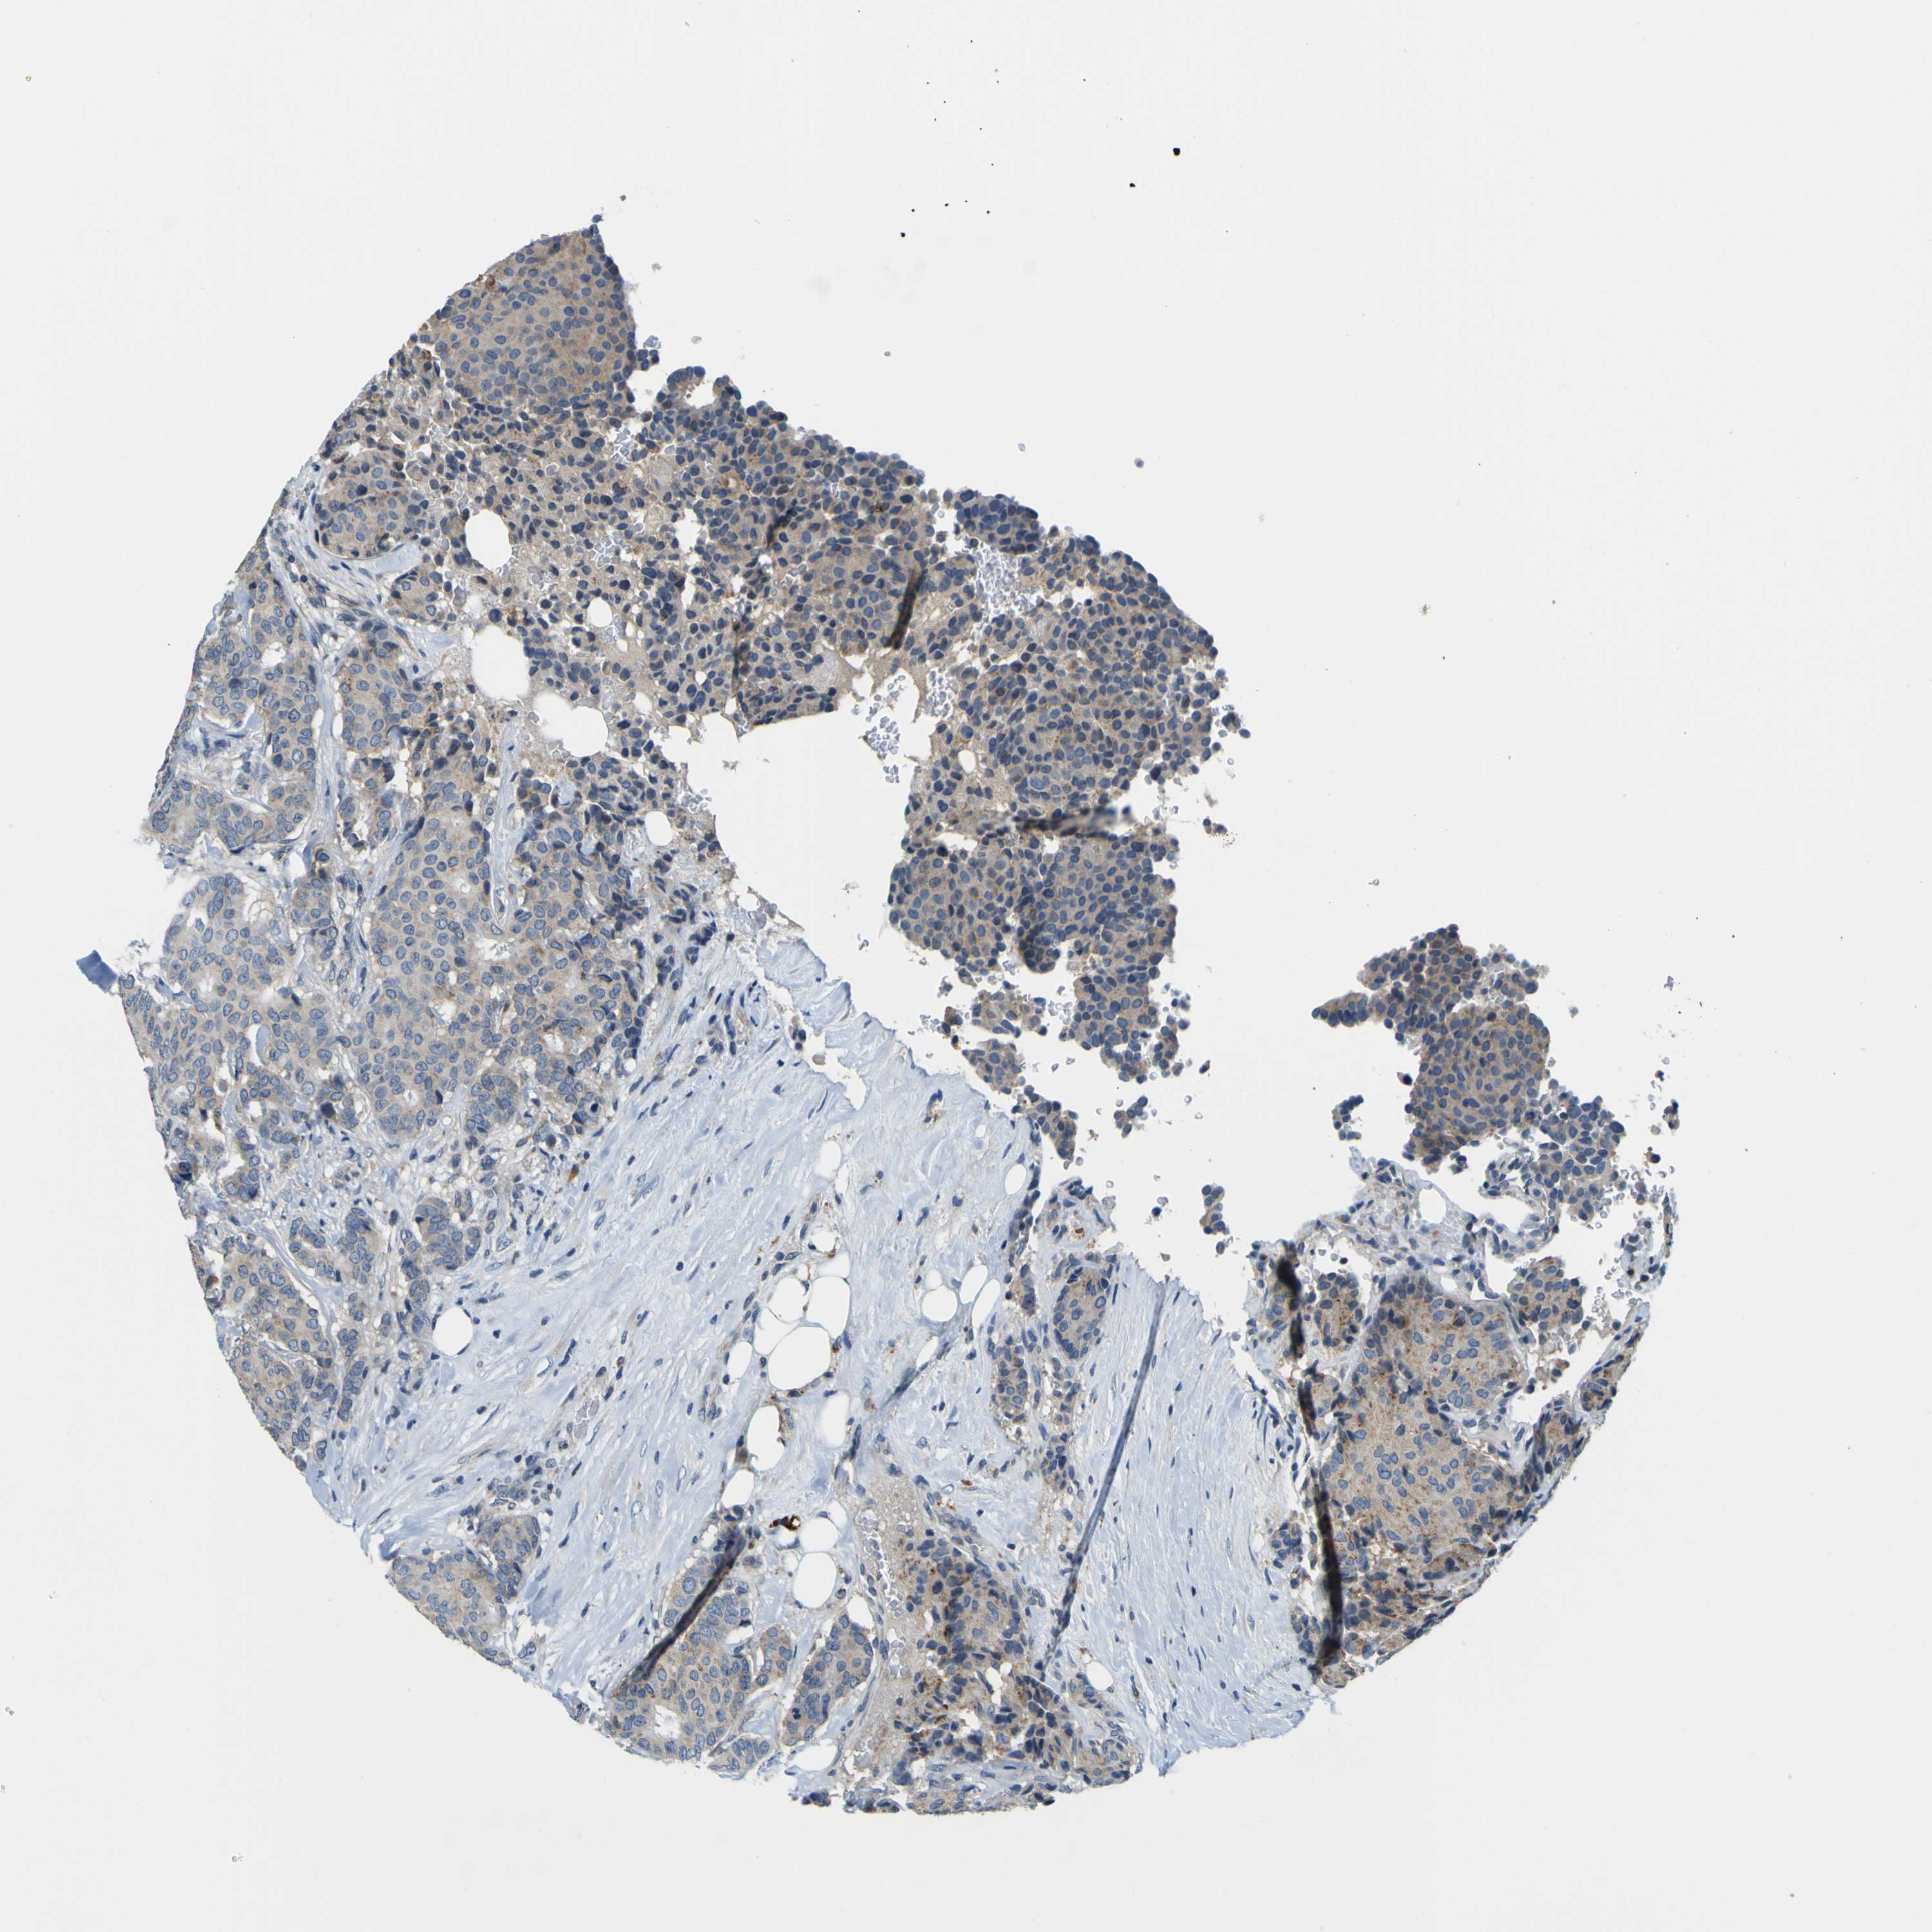

CANCER BREAST CANCER Show tissue menu

BRCA TCGA BRCA VALIDATION PROTEIN EXPRESSION